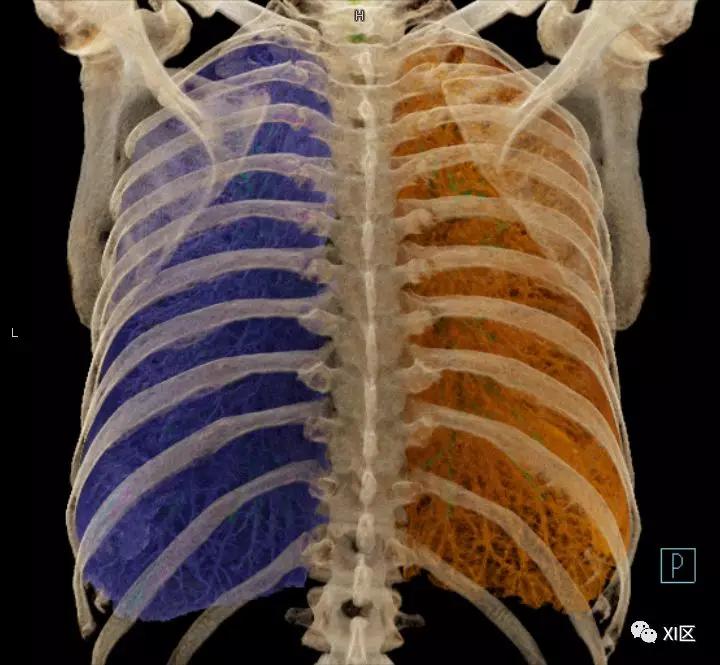

气管支气管树与两肺融合显示

气管树与左右肺的关系